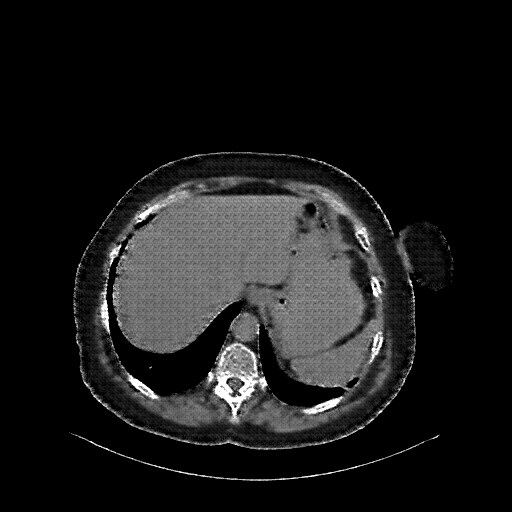

Reconstructed NATIVE CT scan (cycle consistency)

No window - Raw intensity values

Lung window (WL -600, WW 1500 β†’ Low βˆ’1350, High +150)